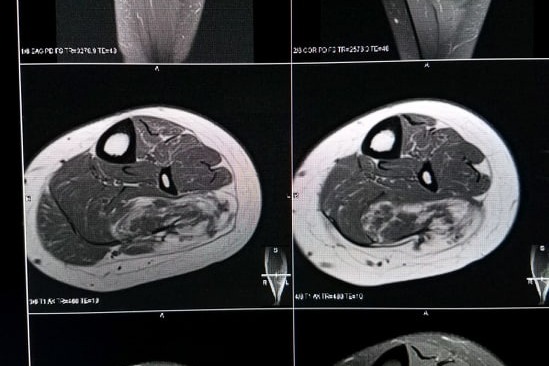

This is another patients FAVA below that was removed but over time grew back.